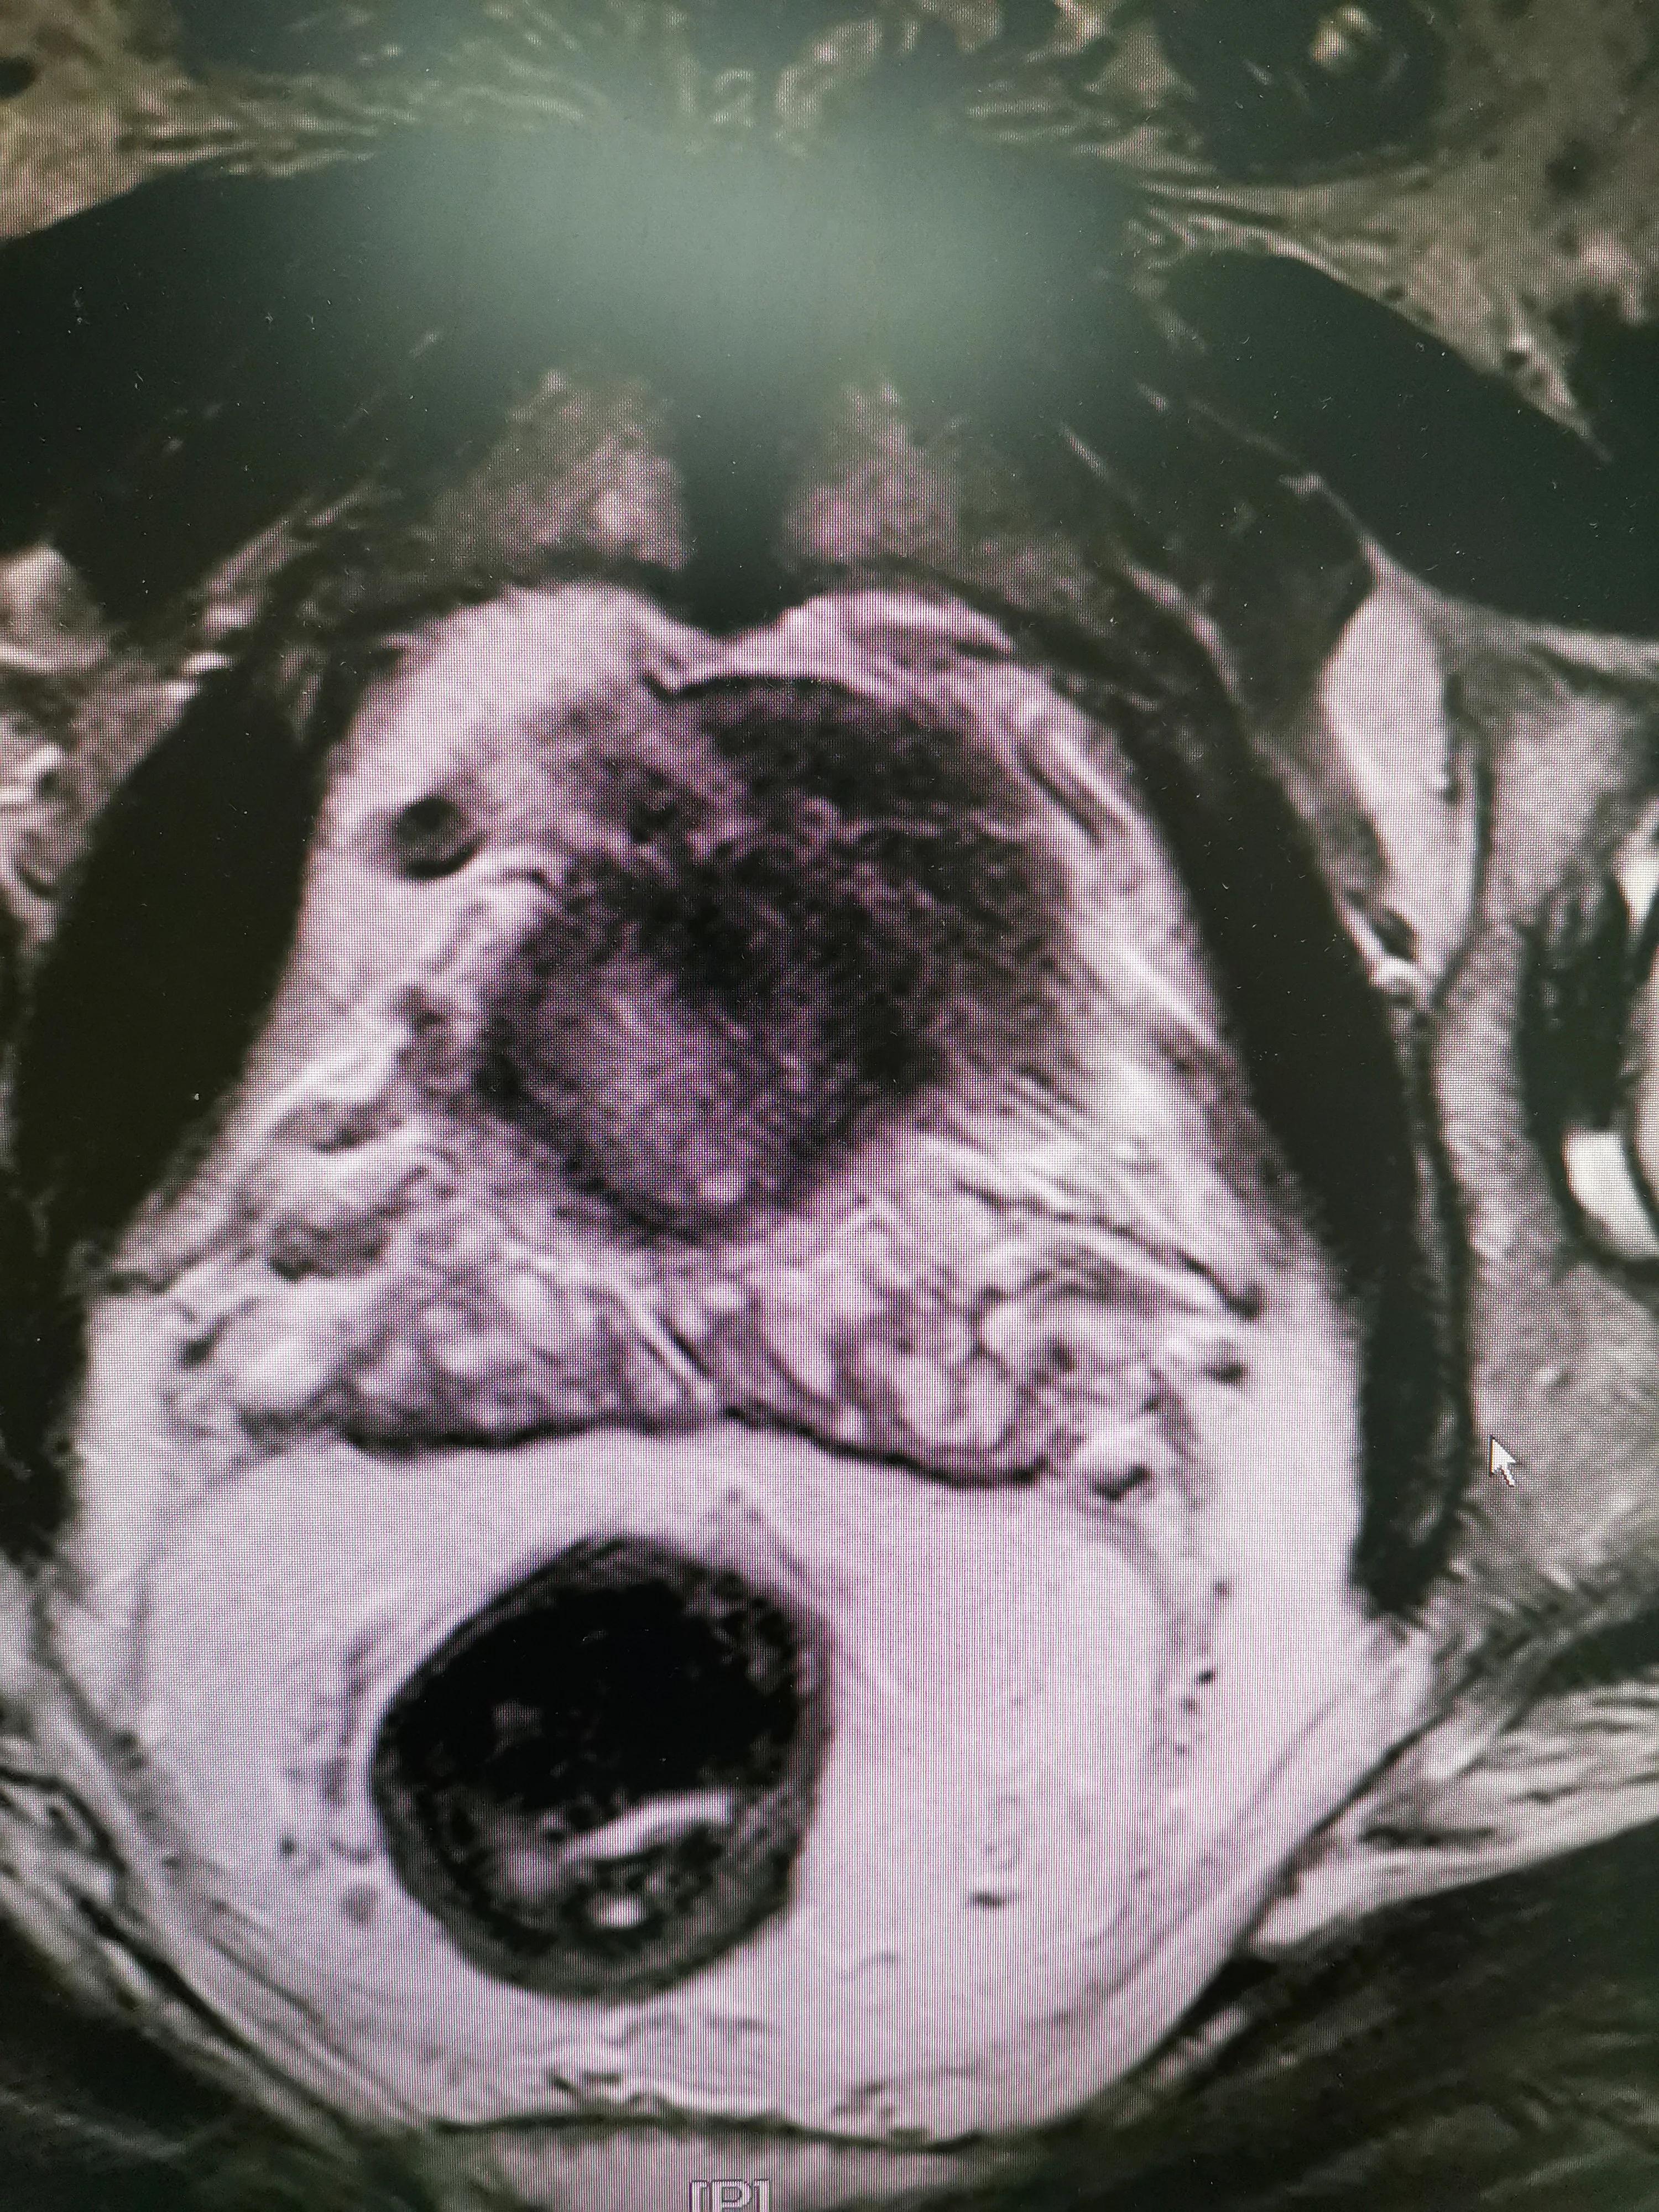

Color Doppler ultrasound of the prostate (especially transrectal ultrasound) allows for an accurate assessment of the prostate's size and structure, determines the presence of inflammatory changes, and identifies any masses, nodules, or calcifications.